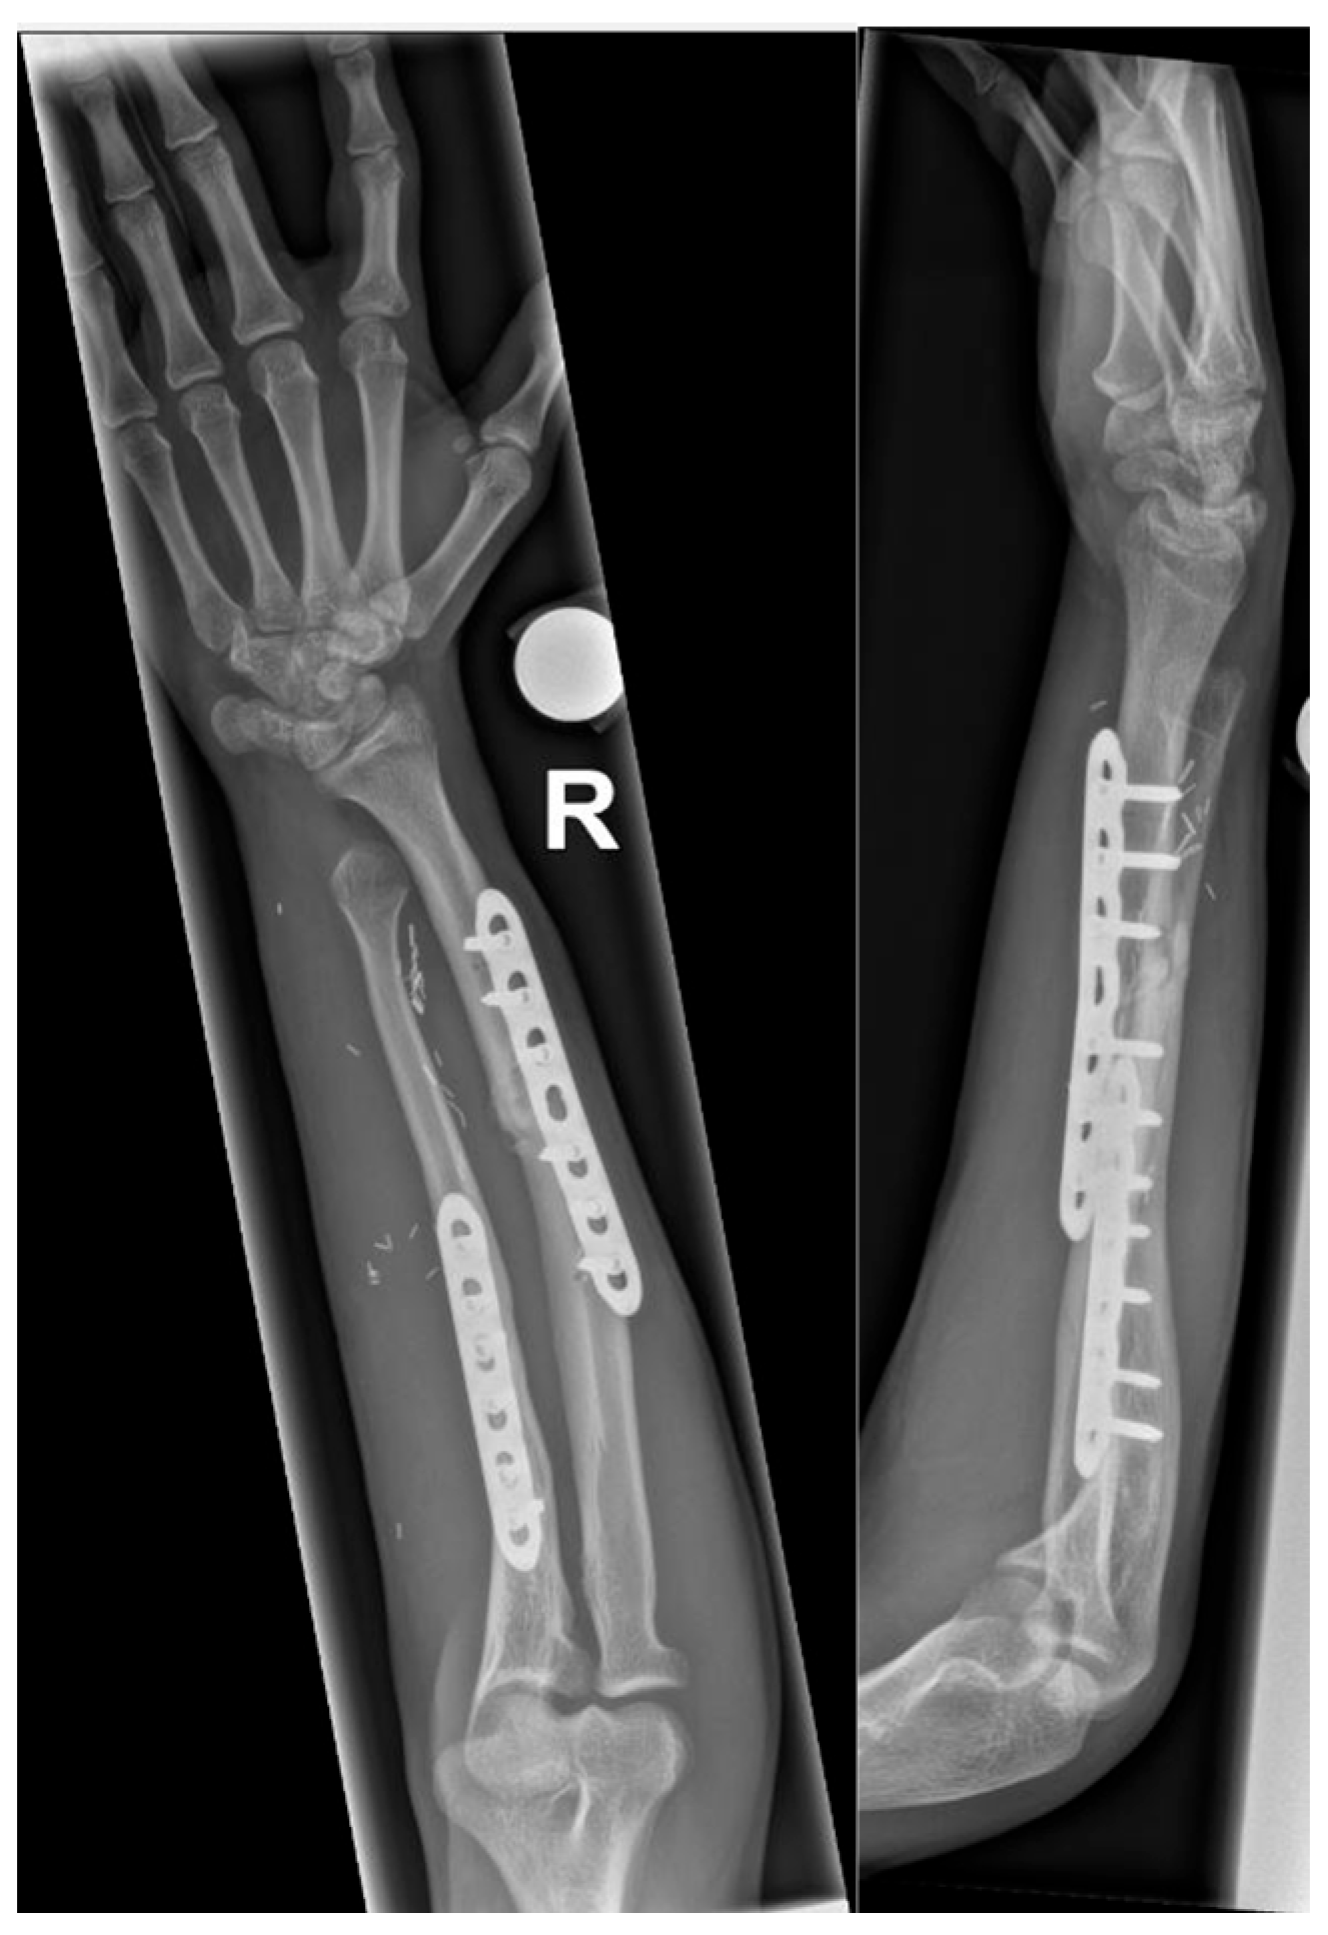

2. Case Report

2.1. Case Report